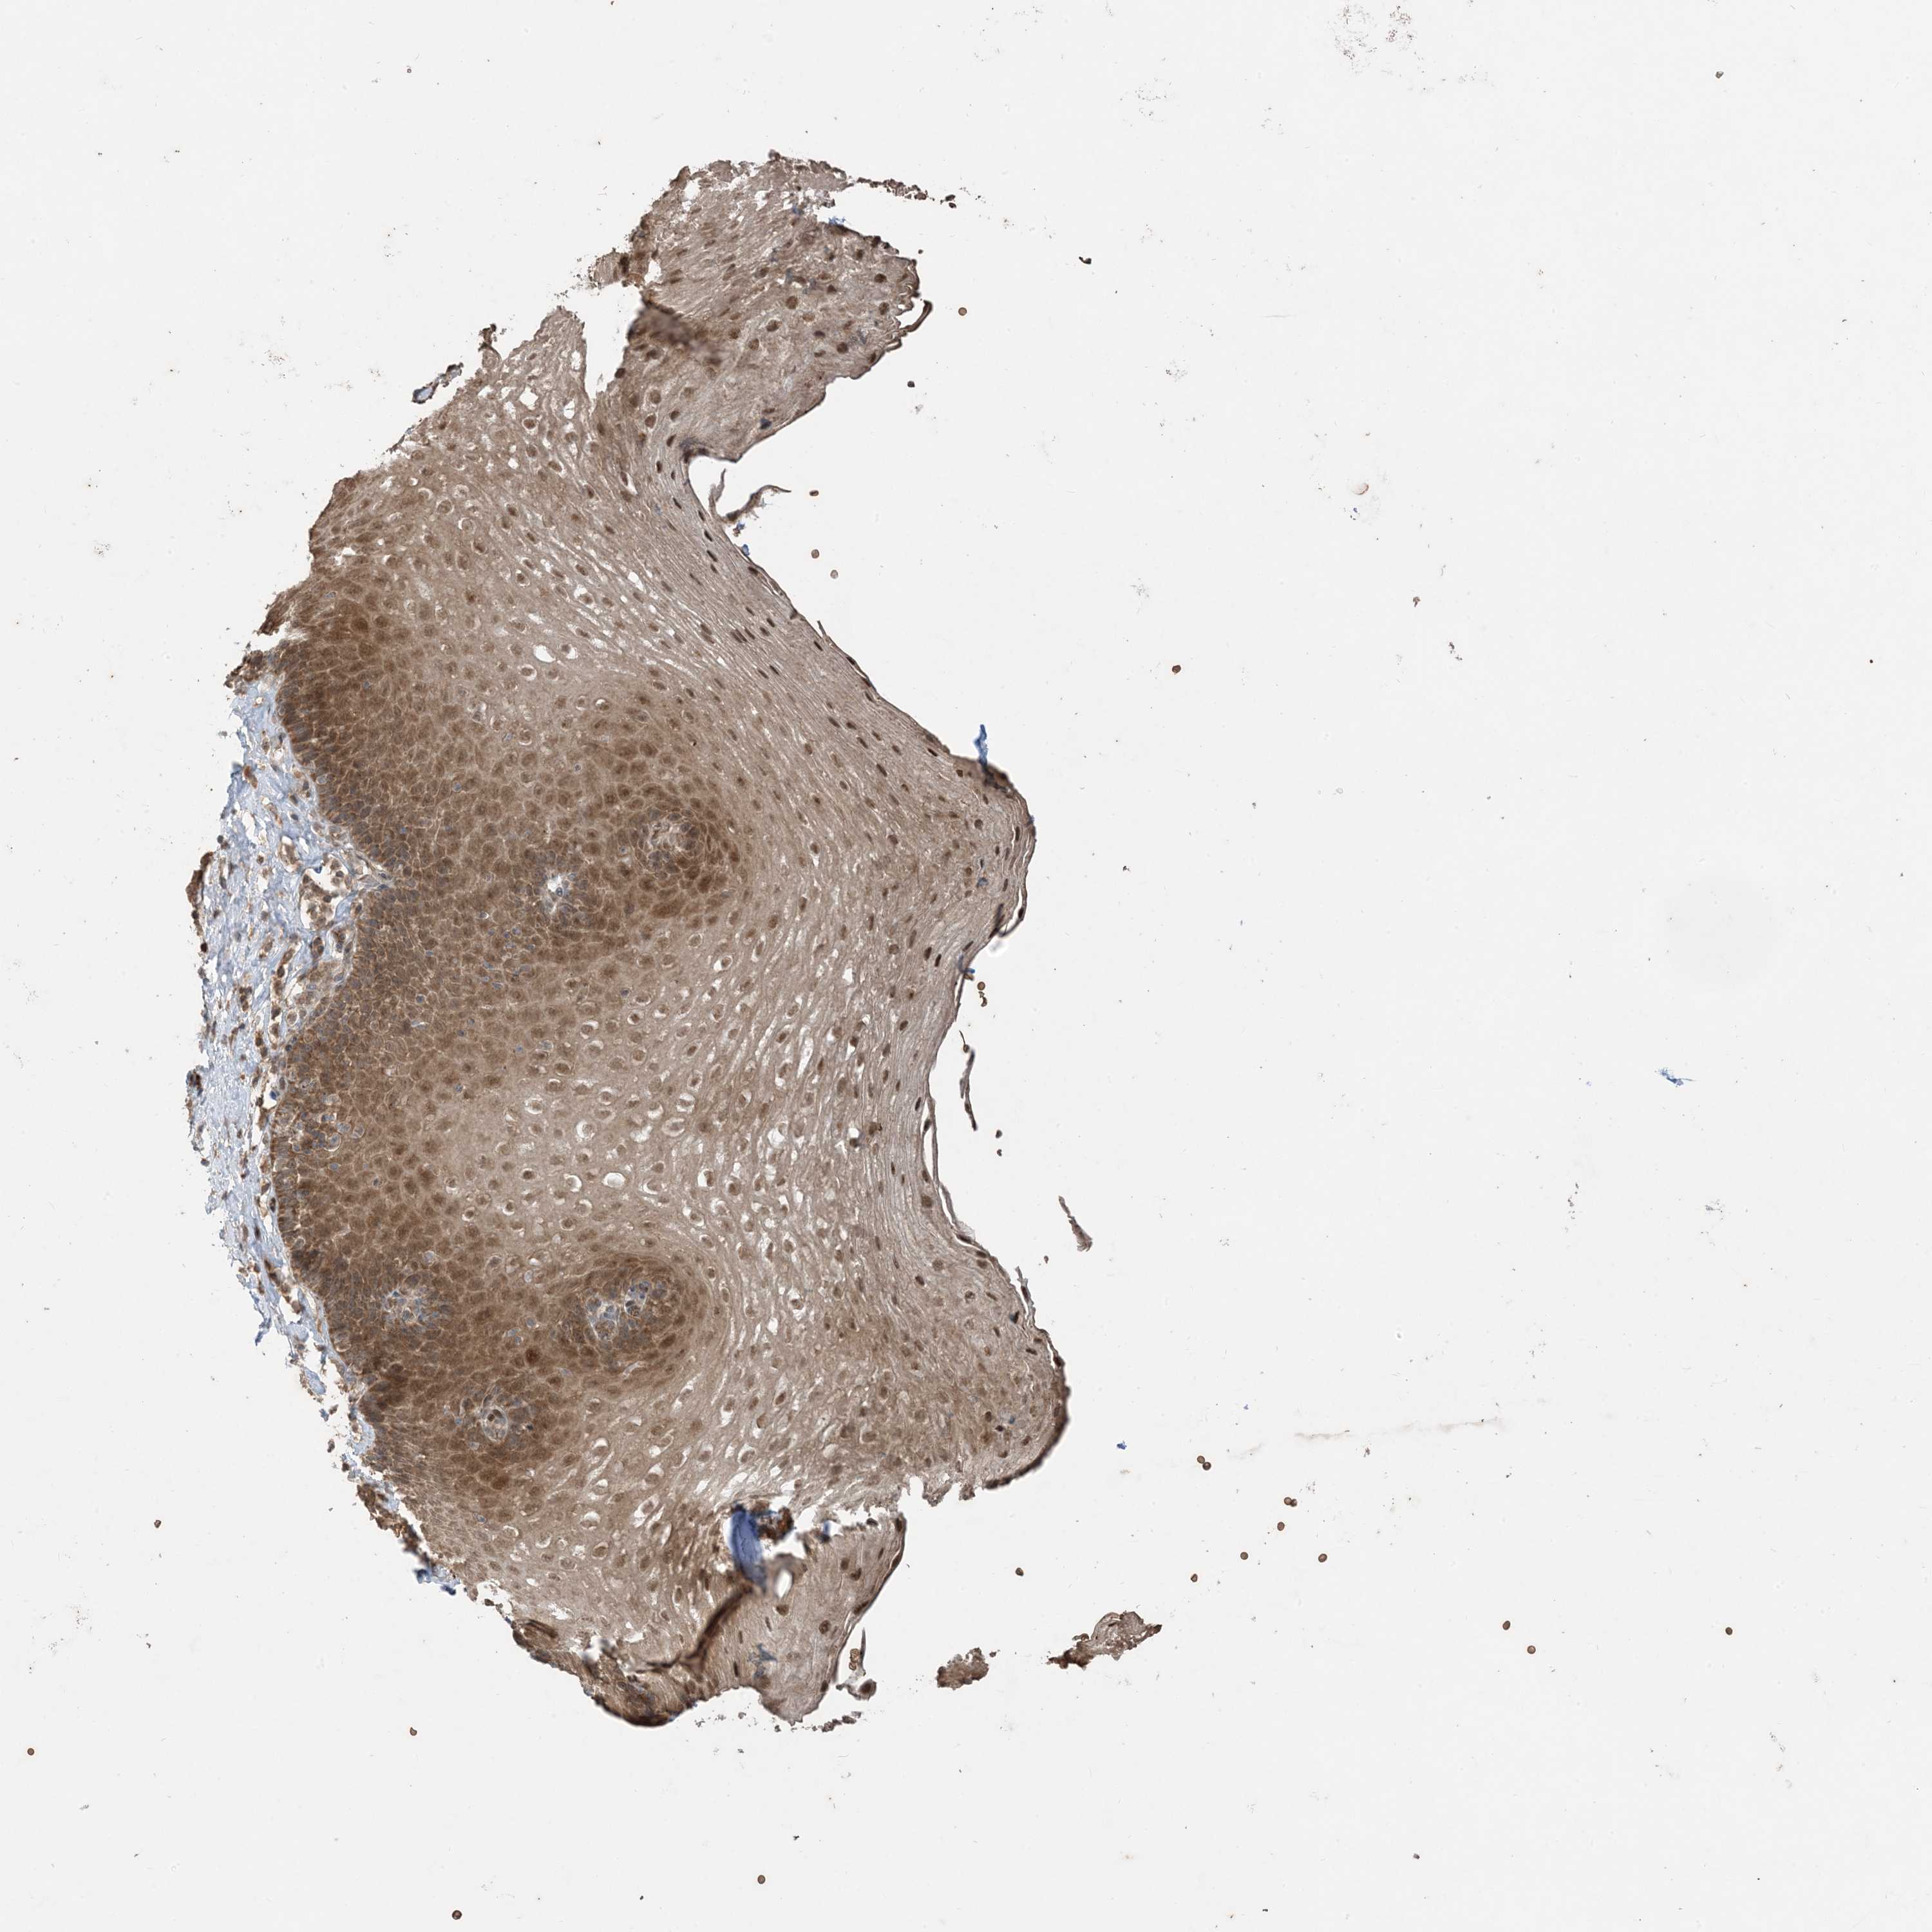

ESOPHAGUS - Antibody stainingi

Antibody staining in the annotated cell types in the current human tissue is reported as not detected, low, medium, or high, based on conventional immunohistochemistry profiling in selected tissues. This score is based on the combination of the staining intensity and fraction of stained cells.

Each image is clickable and will lead to virtual microscopy that enables deeper exploration of all samples and also displays staining intensity scores, fraction scores and subcellular localization as well as patient and tissue information for each sample.

Antibody HPA032057

Squamous epithelial cells Medium